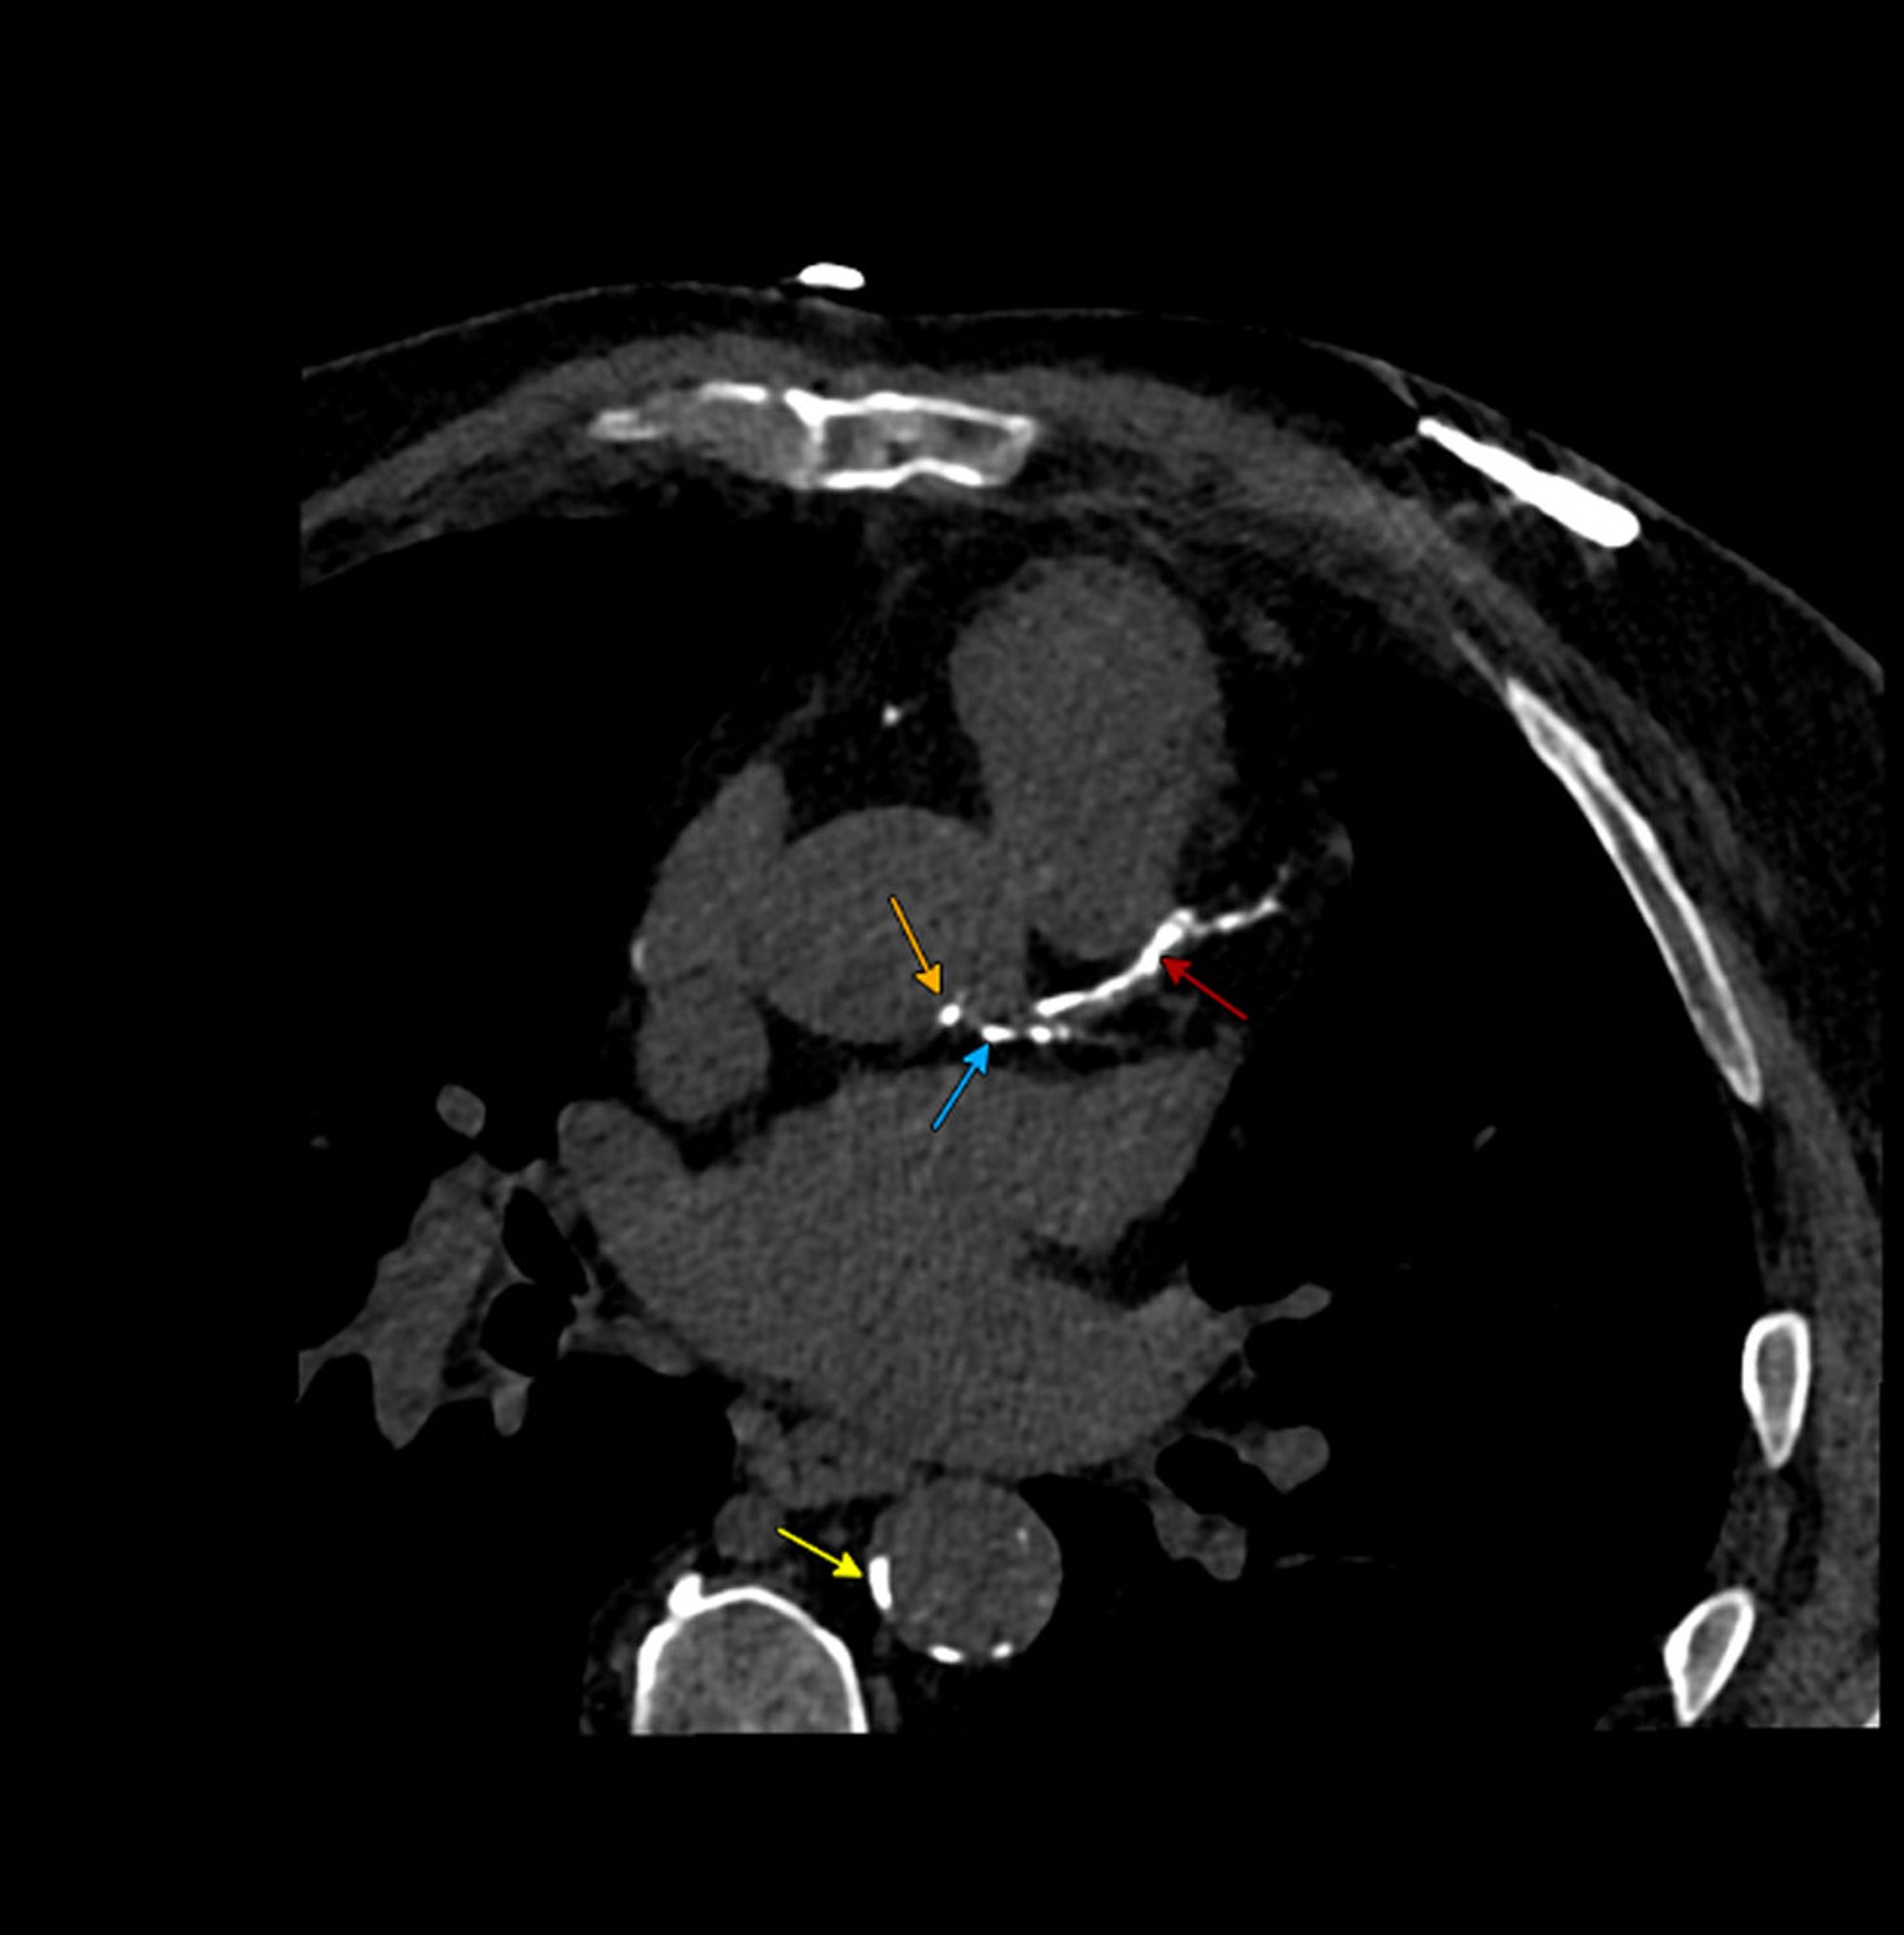

Calcified Atherosclerosis on Calcium Scoring Computed Tomography (CT) Scan

This calcium scoring CT scan shows calcified atherosclerosis in the following structures:

Red arrow: Left anterior descending coronary artery

Blue arrow: Left main coronary artery

Orange arrow: Ascending aorta near the left main ostium

Yellow arrow: Descending aorta

Image courtesy of Attila Feher, MD, PhD.